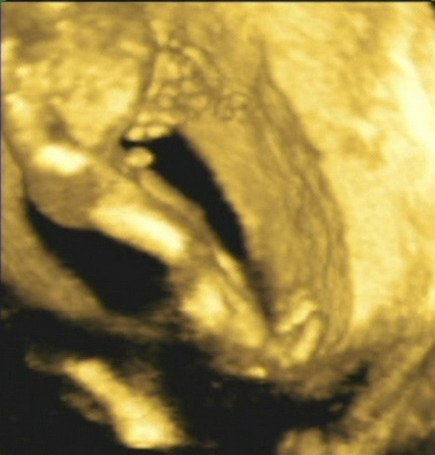

Ezek szerint rendesen mozgott a Babóca a CTG alatt? Én annyira élveztem a CTG-ket mindig, ahogy hallottam, hogy ver Marcikám kis szíve